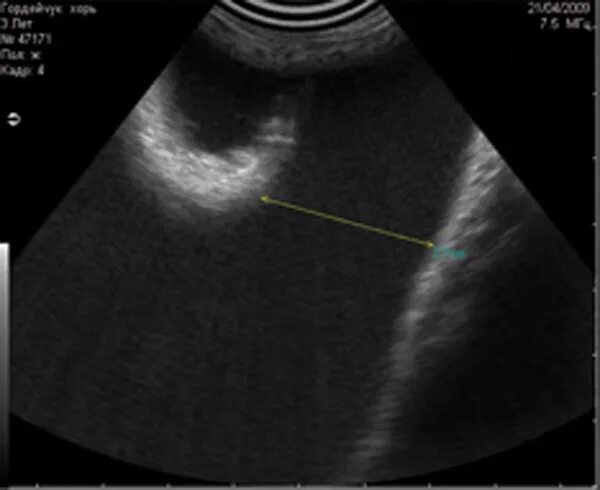

Анэхогенное включение неправильной формы